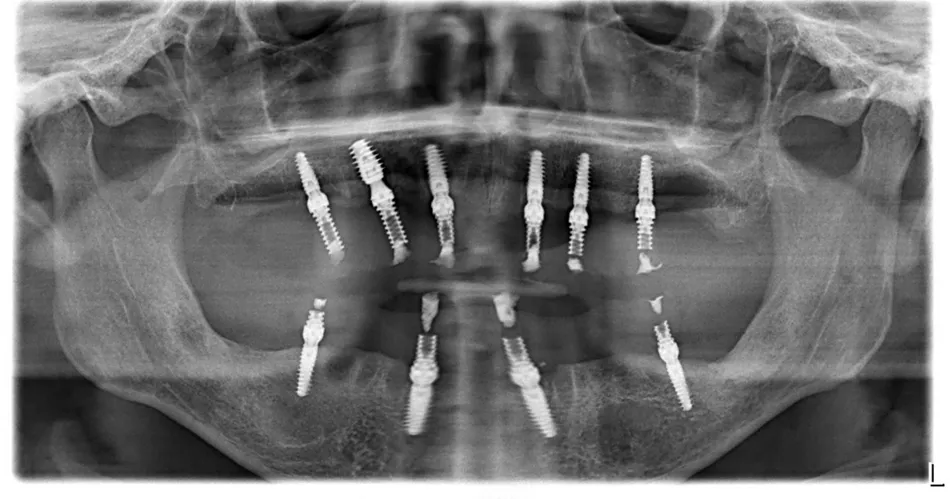

1. OPG showing peri-dental bone involvement and sufficient residual bone for implant placement.

19. Radiographic control (OPG) showing the perfect adaptation of bridges after screwing.